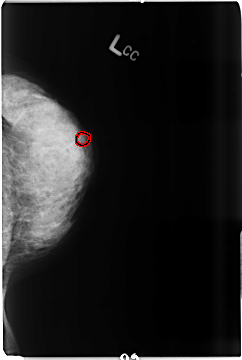

B_3516_1.LEFT_CC

LEFT_CC LINES 4672 PIXELS_PER_LINE 3144 BITS_PER_PIXEL 12 RESOLUTION 50 OVERLAY

FILE: B_3516_1.LEFT_CC.OVERLAY

TOTAL_ABNORMALITIES 1

ABNORMALITY 1

LESION_TYPE CALCIFICATION TYPE PLEOMORPHIC DISTRIBUTION CLUSTERED

ASSESSMENT 4

SUBTLETY 3

PATHOLOGY MALIGNANT

TOTAL_OUTLINES 1

BOUNDARY